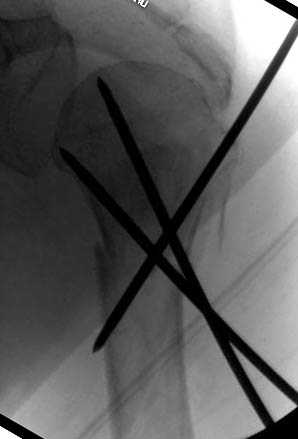

На 20-е сутки снял гипс, одел фиксирующюю

ортопедическую повязку. Вот контроль. Как видно, стояние хорошее, уже формируется костный мозоль.

Думаю еще недели 3 продолжать фиксацию.

-Головка плеча в небольшом варусе или это

проекционное?

Да, там имеем небольшой варус, надеемся, что в будущем проблемы не будет.